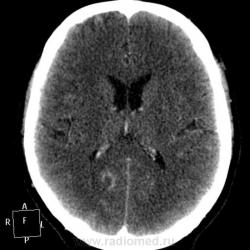

Мужчине 67 лет. У меня нет четкого мнения об изменении в правой затылочной доле. Ваше мнение?

"Непонятная штука в затылочной доле"-вероятнее артерио-венозная мальформация.Гиподенсная зона,прилежащая к ней-отдаленное последствие кровоизлиния из АВМ.

Может кавернома.

Склоняюсь к АВМ, прослеживается приводящий и отводящий сосуды. Не совсем понятно понижение плотности между сосудистыми петлями (может, коллега gar70 прав/а). Рекомендовала МРТ после выписки из сосудистого отделения (у нас такие вещи, что бы из сосудистых аномалий ни было, не оперируют).